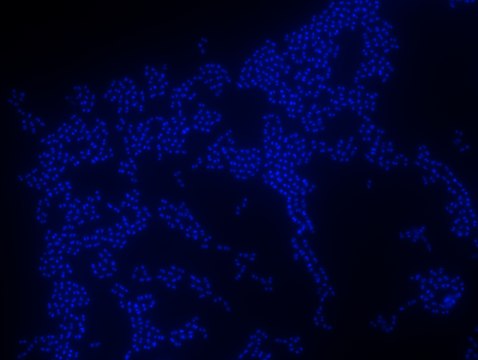

Enterococcus faecium FISH probe – ATTO 488

Probe for fluorescence in situ hybridization (FISH), recognizes Enterococcus faecium cells

• Visualize, identify, and isolate E. faecium cells.